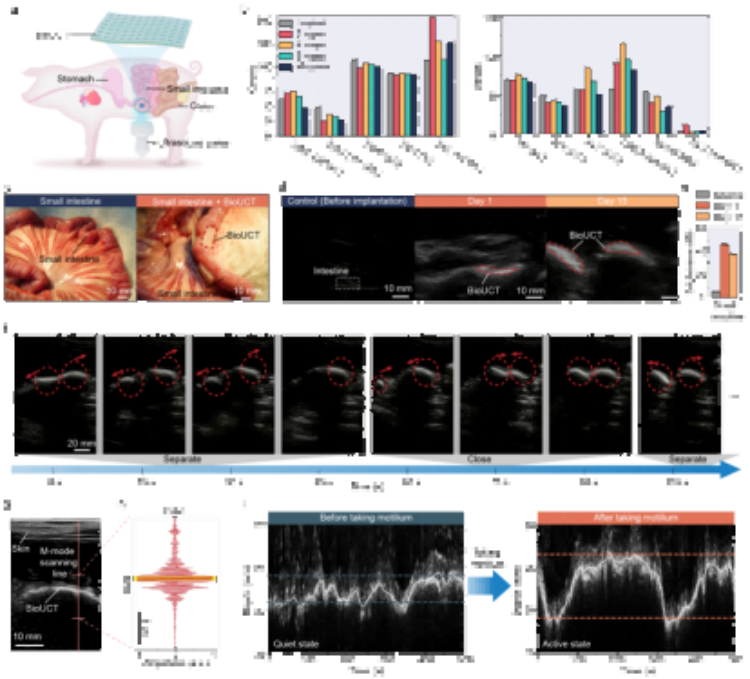

二、應用場景

在對豬腸道蠕動幅度監測的驗證實驗中,操作人員通過臨床通用的超聲成像設備成功追蹤到服藥前后腸蠕動幅度的變化(3.13mm→7.59mm)。該技術未來可結合可穿戴超聲設備,實現患者居家監測,特別適用于:小腸切除術后并發癥預警慢性腸梗阻患者長期管理胃腸動力藥效評估。

圖5. 通過BioUCT進行活體動物腸道運動監測。